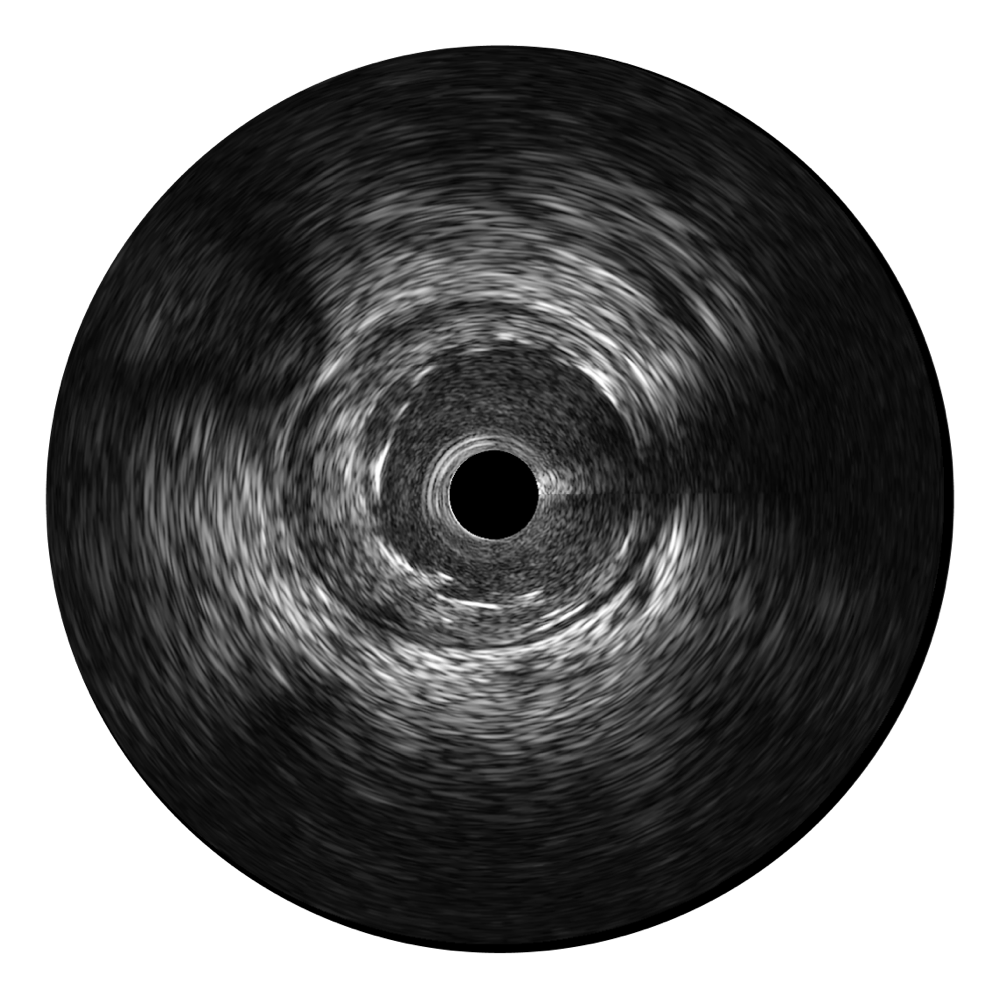

米兰官方网站宽频IVUS图像

传统IVUS图像

对比传统IVUS导管成像,米兰官方网站宽频IVUS图像的近场支架梁显影更细腻,远场中膜外血管仍清晰可辨,兼顾远中近,兼顾分辨力与穿透深度